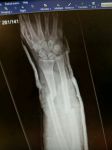

Not really ok, damage to front of my bike,

double open fracture to right foearm, broken and dislocated left thumb, stitches to right knee!

Loose horse ran straight over me even though i had stopped in the road!

Damn looks nasty, I snapped my humerous through in my upper right arm years back and it seemed to take forever for the bones to nit back together. Yes you should most definitely make the owner PAY! Poor TTR cry